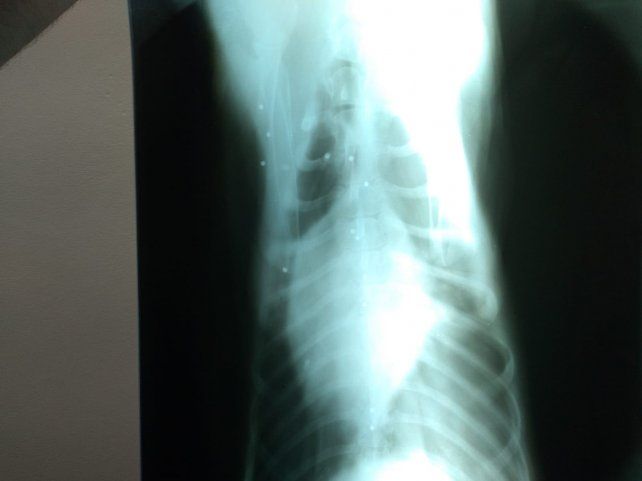

Respecto del estado del animal herido, el médico veterinario Ernesto Sobrero dijo que ingresó este viernes a las 8:30 y se le practicaron diferentes estudios para conocer su real estado de salud. "El panorama es complicado porque presenta perforaciones por arma de fuego. Al ser escopeta, tiene un montón de perdigones alojados en distintas partes del cuerpo y órganos. Estamos tratando de estabilizarla y está respondiendo bien, pero es imposible acceder a la zona donde están alojados los plomos por la cantidad de lesiones. y porque están alojados en lugares de difícil acceso", explicó. Finalmente dijo a LT 39 que no puede dar un pronóstico sobre su recuperación.